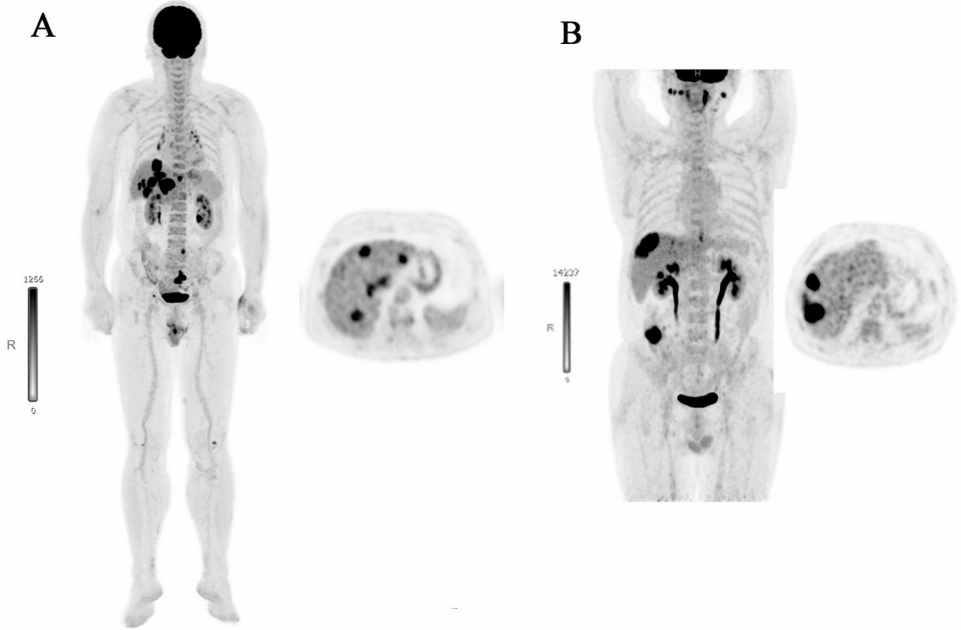

本研究针对全身(Total-body, TB) 18F-FDG PET/CT系统,通过理论模型与临床验证相结合的方式,提出四种典型临床场景下的扫描策略优化方案。研究人员系统评估了固定工作时间、预设放射性示踪剂活度、多剂量方案组合及动态/静态扫描整合等场景,发现1/3剂量方案在37,000-148,000 MBq活度范围内可实现最高患者流通量(52-72例/日),而整合多剂量方案可降低37%示踪剂消耗。临床验证显示TB PET/CT单日最大流通量达60例,是传统设备的2.7倍,为高负荷医疗中心提供了兼顾效率与成本的最优解。

复旦大学附属中山医院核医学科团队在《EJNMMI Research》发表的研究,系统探索了TB PET/CT的临床效率优化路径。研究通过建立理论模型量化分析了四种典型场景:固定8小时工作制下的最大流通量、预设总活度下的最优方案、多剂量组合的活度节约策略,以及动态/静态扫描的整合时序。临床验证中,团队在真实医疗场景下完成单日60例全剂量扫描,证实理论模型的可靠性。研究发现1/3剂量(1.11MBq/kg)方案在1-4居里总活度下能支持52-72例检查,而将动态扫描安排在常规扫描序列末端可降低15%活度消耗。这些成果为TB PET/CT的临床资源配置提供了精确的数学工具。

实际测试数据与理论预测高度吻合:全剂量组60例(理论60例),1/3剂量组48例(理论43例)。图像质量评估显示,即使0.37MBq/kg超低剂量仍满足诊断需求,证实TB系统的灵敏度优势。